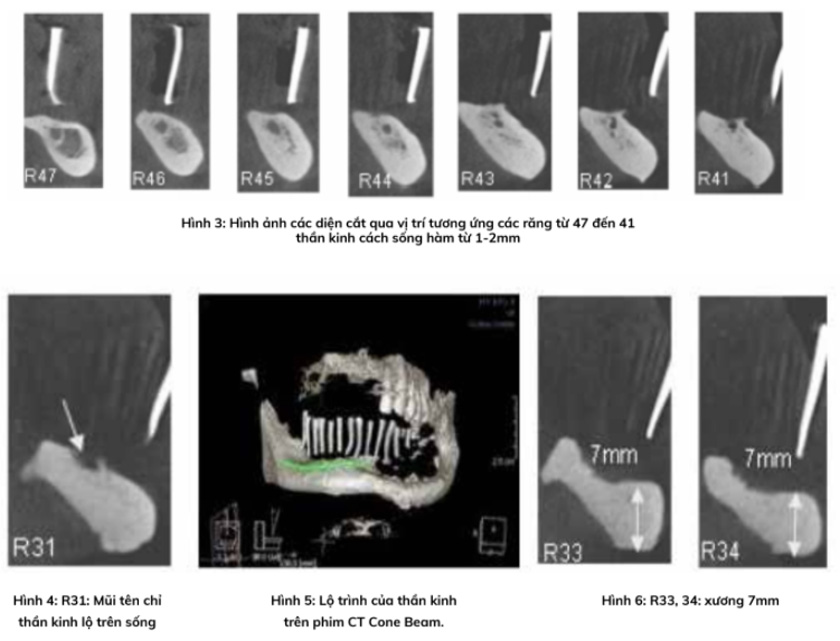

Báo cáo mô tả một trường hợp lâm sàng dời thần kinh ổ răng dưới(*), kết hợp ghép xương mào chậu tăng chiều cao xương(*), đặt 4 implant(*) và phục hình toàn hàm nâng đỡ trên implant(*) ở một bệnh nhân nam 59 tuổi có tình trạng xương hàm dưới tiêu xương ở mức độ trầm trọng.

Kết quả sau điều trị: Có tình trạng tích hợp xương tốt ở cả 4 implant, khôi phục chức năng ăn nhai tốt, dị cảm môi hồi phục hoàn toàn sau 4 tháng, bệnh nhân hoạt động bình thường 4 tuần sau phẫu thuật lấy xương mào chậu.

Đồng thời, báo cáo cũng xác định tính an toàn của kỹ thuật, mức độ biến chứng về chức năng thần kinh và biến chứng tại vùng mào chậu cho xương ghép.

Phẫu thuật dời thần kinh ổ răng dưới để cấy ghép implant(*), ghép xương mào chậu(*), phối hợp ghép nướu sừng hóa(*) và phục hình nâng đỡ trên implant(*) là phương pháp khả thi và cho kết quả tốt, đặc biệt trong tình huống bệnh nhân bị tiêu xương hàm trầm trọng mà các phương pháp khác không thể áp dụng được.

Tuy nhiên, kỹ thuật này đòi hỏi trình độ chuyên môn cao và tay nghề của bác sĩ thực hiện. Đồng thời, cần giải thích trước với bệnh nhân về những biến chứng có thể xảy ra như dị cảm thần kinh, gãy xương hàm dưới.